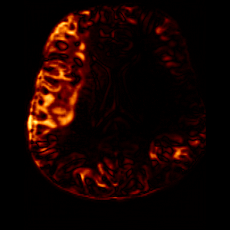

PathologicalHealthyDifferencew/o ACGw/ ACG(a)Refer to captionRefer to captionRefer to captionRefer to captionRefer to captionHealthyPathologicalDifferencew/o ACGw/ ACG(b)Refer to captionRefer to captionRefer to captionRefer to captionRefer to caption

Figure 6: Ablation study of Anatomy Consistency Guidance (ACG): (a) pathology-to-healthy; (b) healthy-to-pathology. Without ACG, edits cause anatomical inconsistencies outside lesions (arrows), whereas ACG keeps modifications lesion-focused.

Anomaly Consistency Guidance. Fig. 6 demonstrates the effectiveness of the proposed Anatomy Consistency Guidance (ACG) on bidirectional editing. Without ACG, the generated brains exhibit noticeable and unrealistic anatomical deformations in non-lesion regions (arrow-indicated), leading to structural inconsistencies between the edited and original brains, as shown in the corresponding difference maps. After incorporating ACG, the model effectively constrains editable modifications within pathological regions, while preserving the remaining anatomy. Tab. 4 further reports their quantitative performances: removing ACG leads to a substantial degradation in all L1, PSNR, and SSIM scores, reaffirming the critical role of ACG in achieving more accurate and structurally consistent reconstructions.